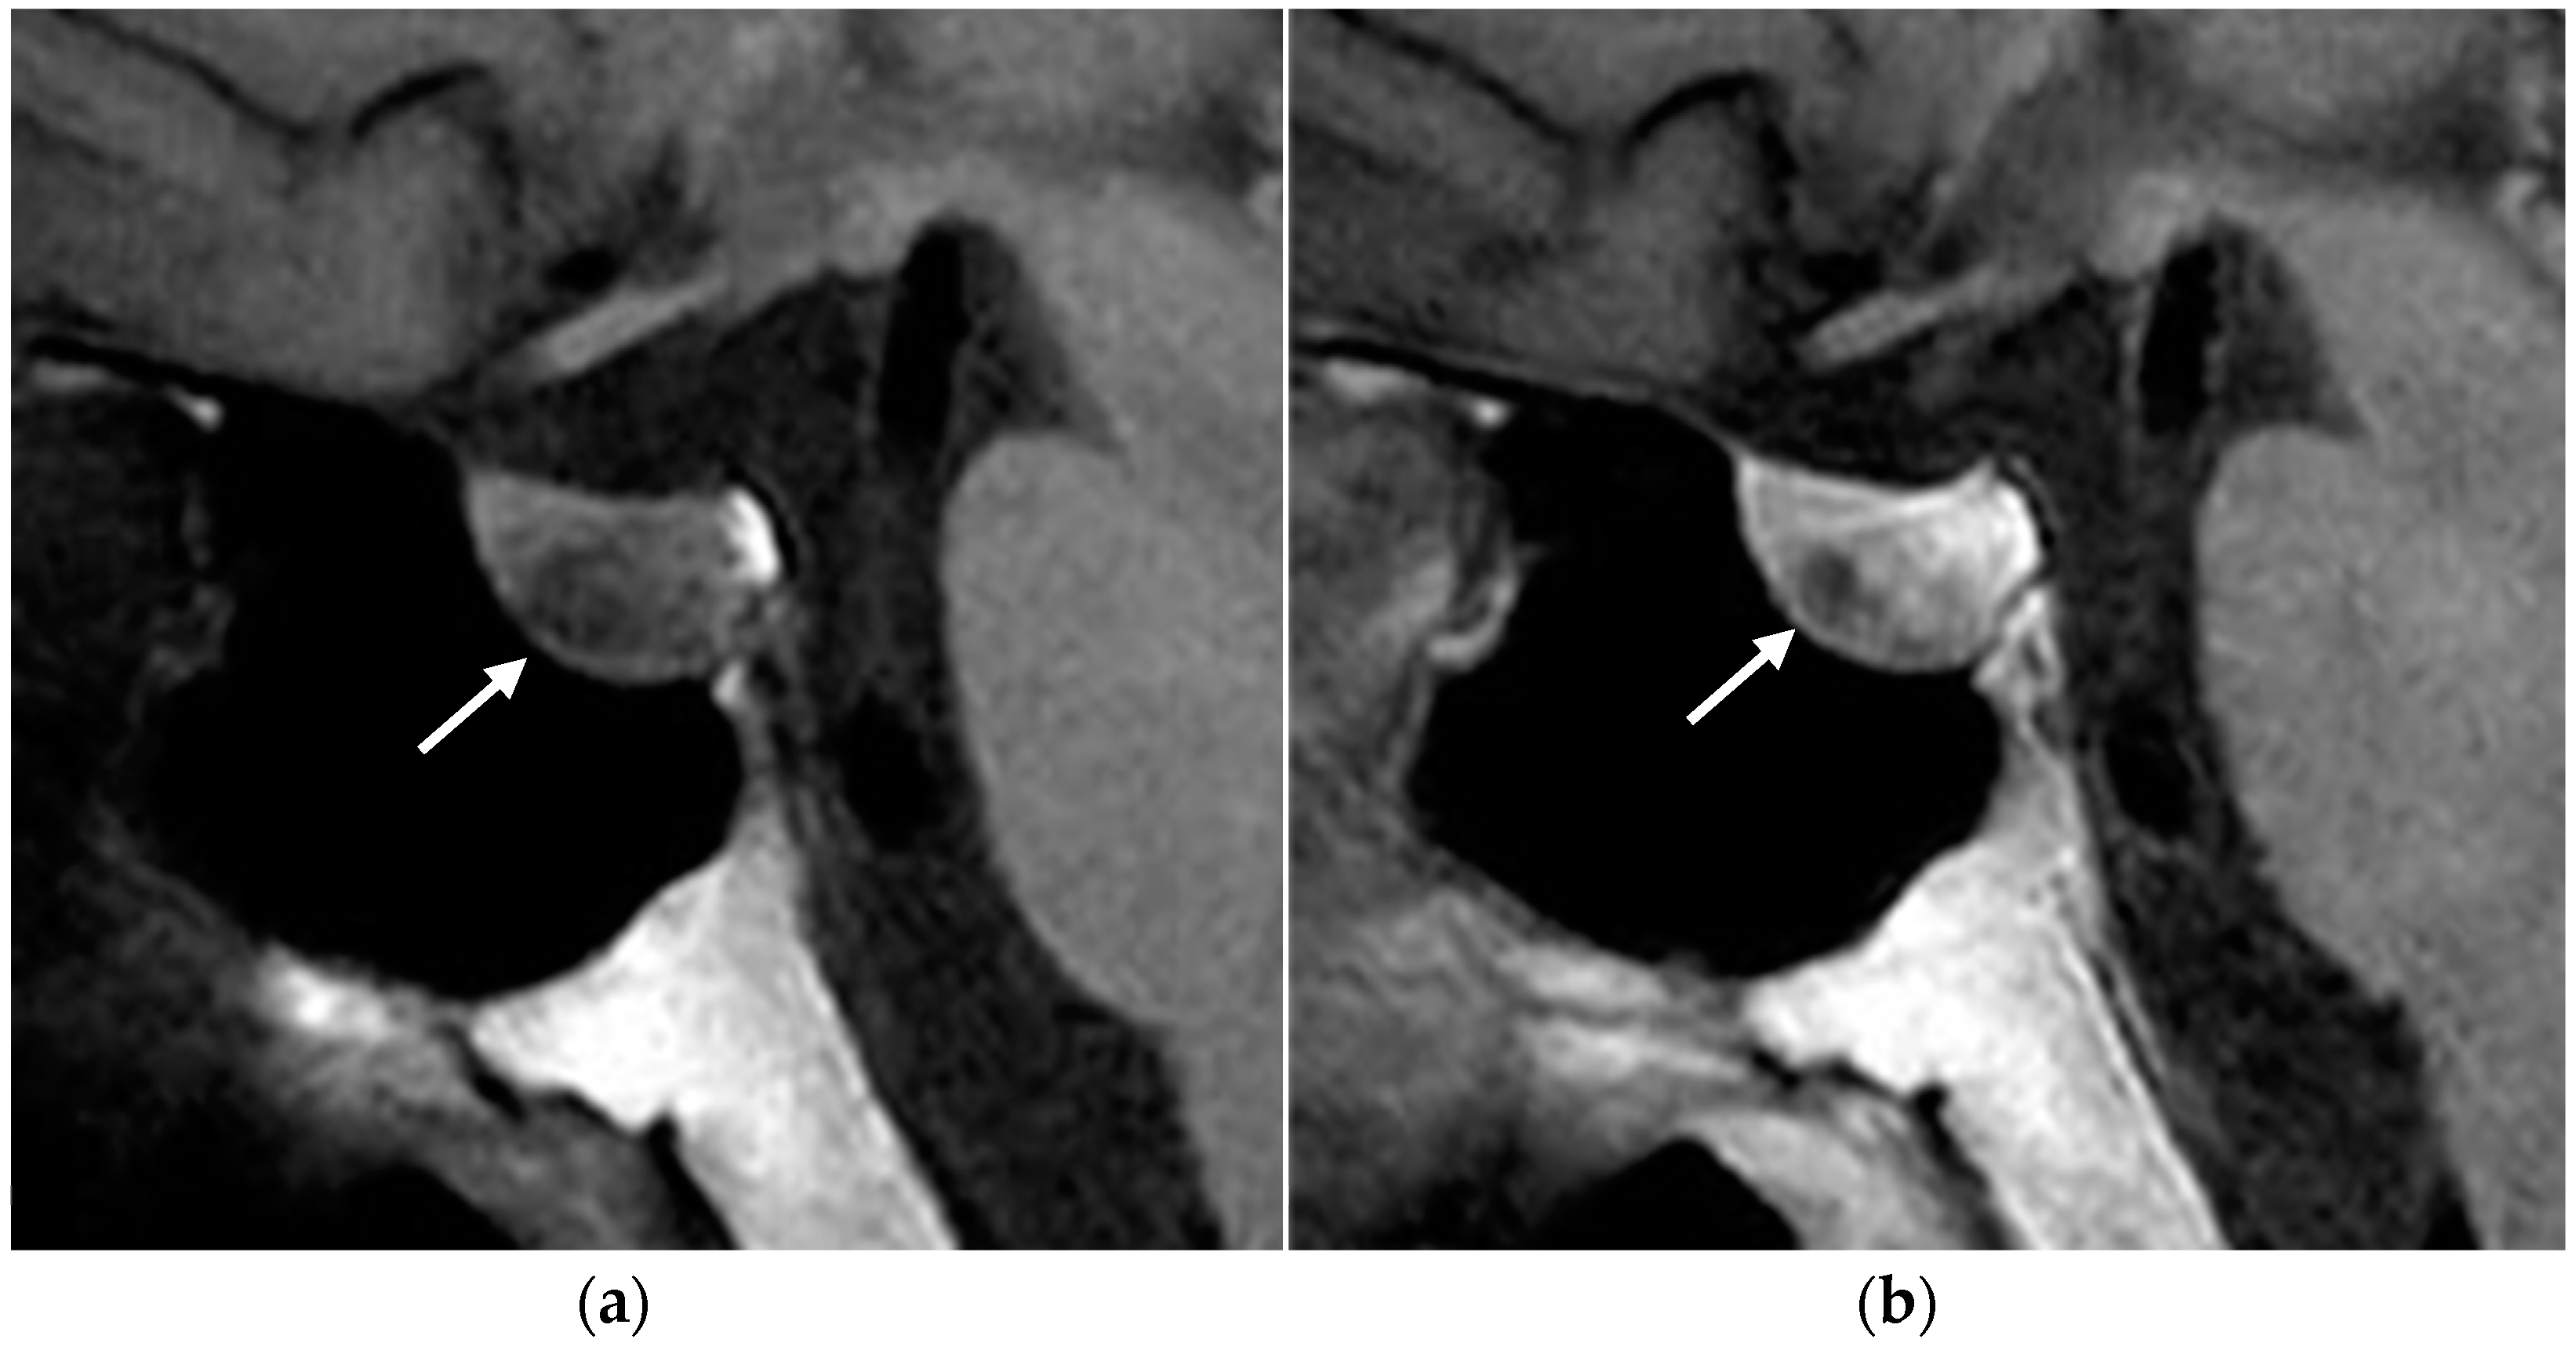

MRI

- Gruppetta, M. A current perspective of pituitary adenoma MRI characteristics: A review. Expert. Rev. Endocrinol. Metab. 2022, 17, 499–511. [Google Scholar] [CrossRef] [PubMed]